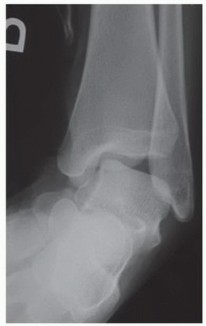

DEFINITION The terminology of osteochondral lesions is not uniform: Transchondral fractures, osteochondral fr…